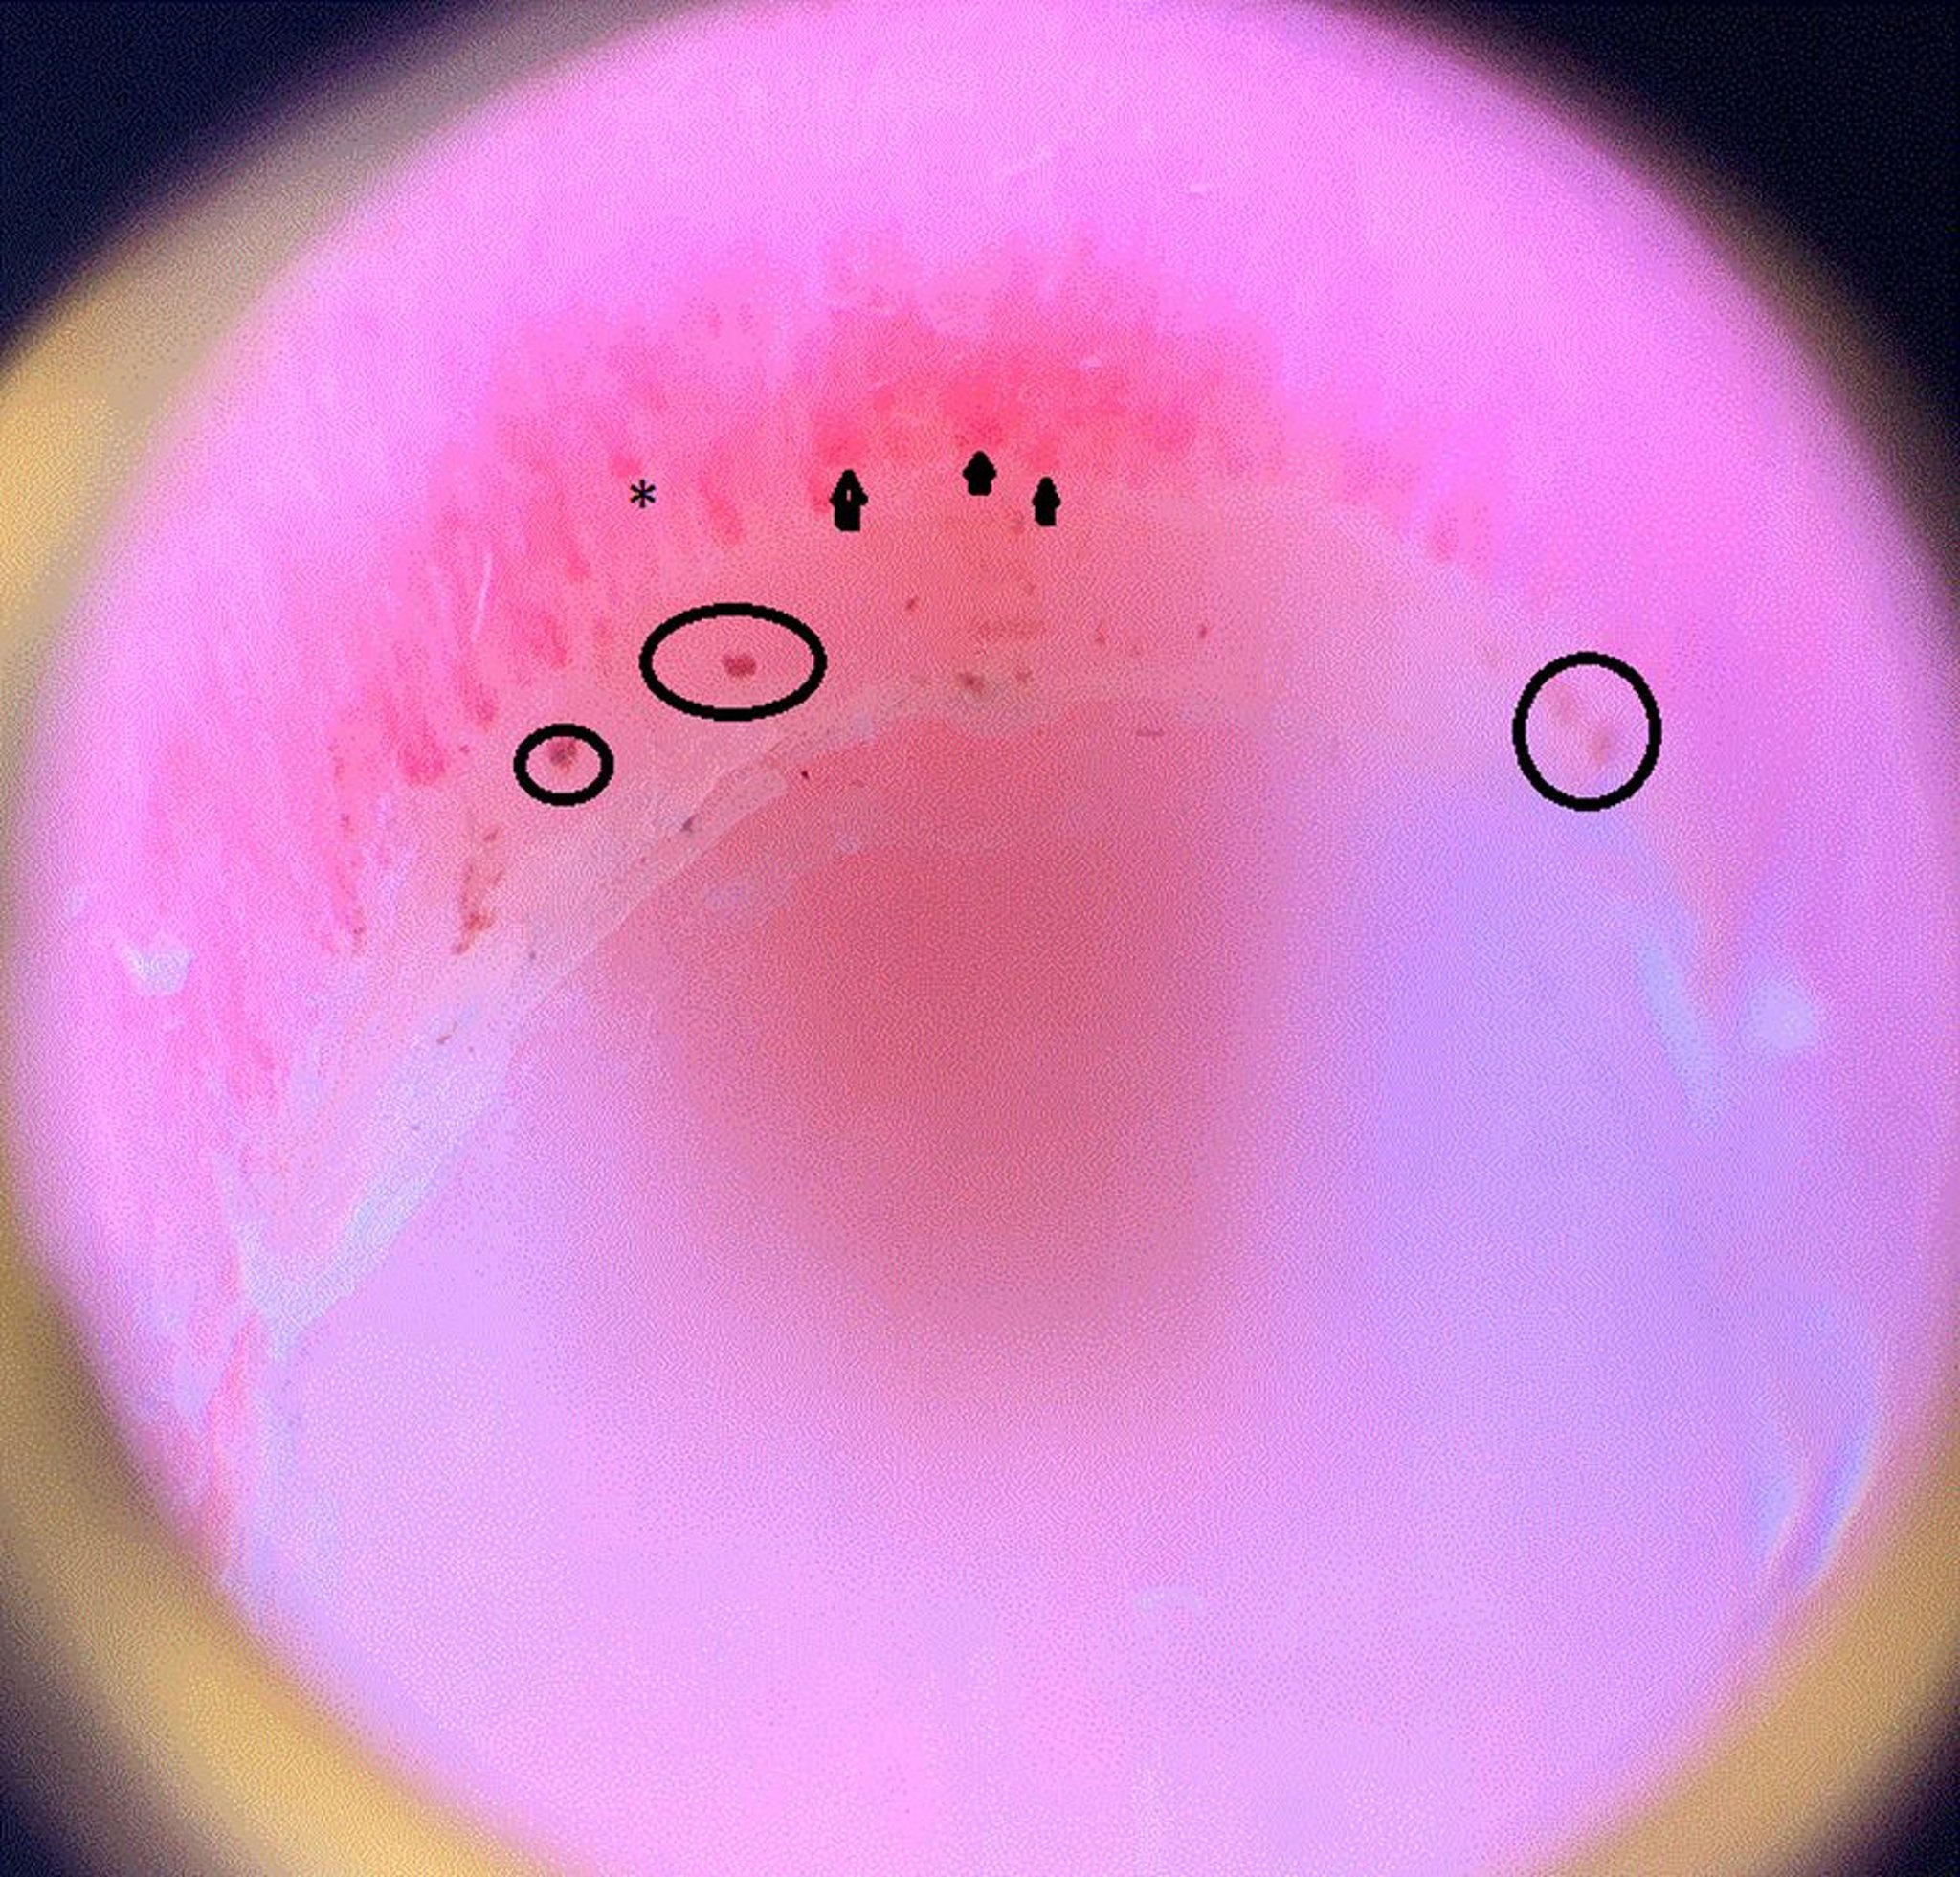

Esta imagen muestra asas capilares dilatadas (puntas de flecha), un área de cierre, que significa que el capilar termina prematuramente y desaparece, por lo que se ve más corto que los otros (asterisco), y hemorragias periungueales (círculos) en el pliegue ungueal de un paciente con esclerosis sistémica.